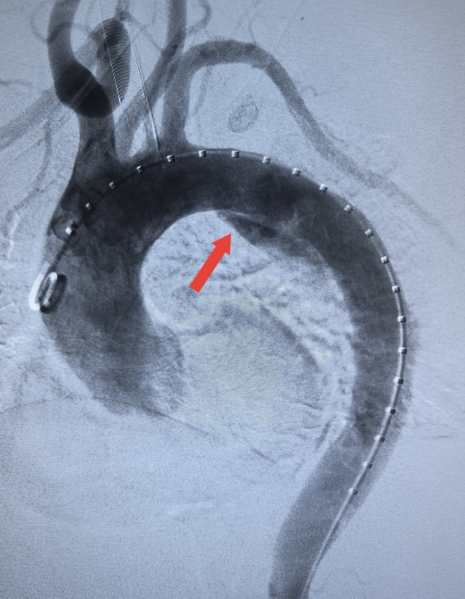

【术中造影】